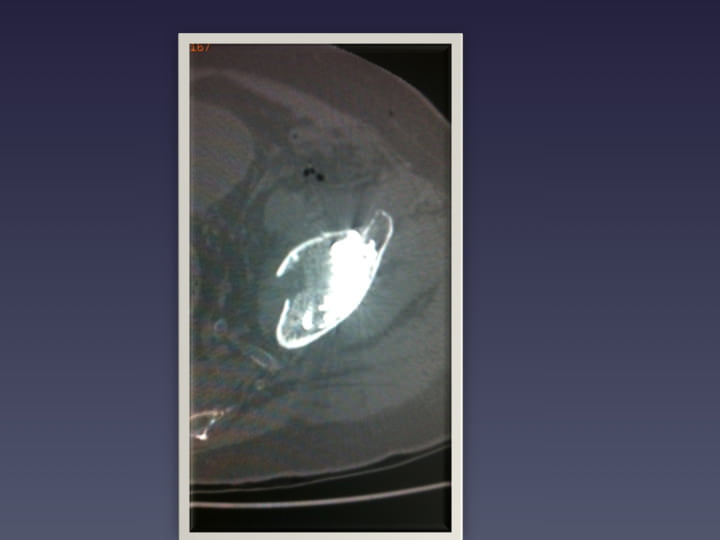

• BASSIN HANCHE

• FRACTURES DU BASSIN

• OSTEOPLASTIE ET OSTEOSYNTHESE SOUS GUIDAGE SCANNER

• OSTEOSYNTHESE

• RSNA 2012 VISSAGE DES FRACTURES COTYLOÏDIENNES

• OSTEOSYNTHESE SOUS SCANNER